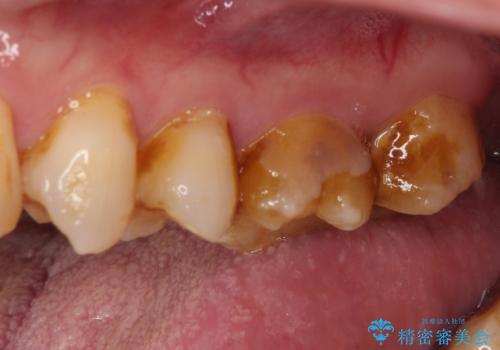

- 食事で堅いものを噛んだ時に歯が欠けてしまったとのことで来院された患者様です。

咬合面に大きな修復物が入っており、その境目から破折し、歯肉の内側の歯根にまで破折が及んでいました。